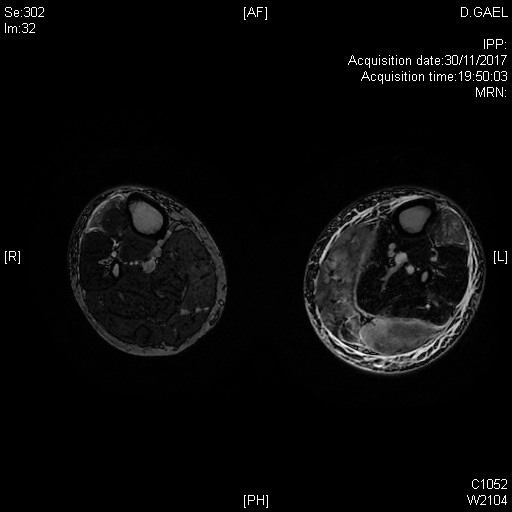

Tableau clinique de polymyosite avec atteinte clinique et IRM des deux jambes